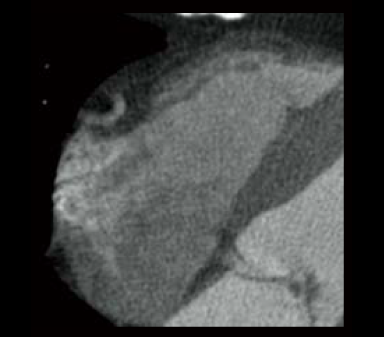

In cardiac CT examinations, the various factors such as heart rate and heart movement affect image quality. With conventional image reconstruction methods, unfocused coronary arteries and artifacts caused by motion could occur, resulting in images not meeting the expected quality, which could affect the diagnosis. To help resolve these problems, Fujifilm developed Cardio StillShot, which calculates the direction and amount of movement of the subject in four dimensions based on the raw data collected during cardiac CT examinations, and corrects it during image reconstruction to achieve an effective time resolution of 28 msec.*1 The effective time resolution contributes to improved diagnostic capability by providing high-definition focused clinical images with less motion artifacts even in patients with a high heart rate.

Cardio StillShot: OFF

ON